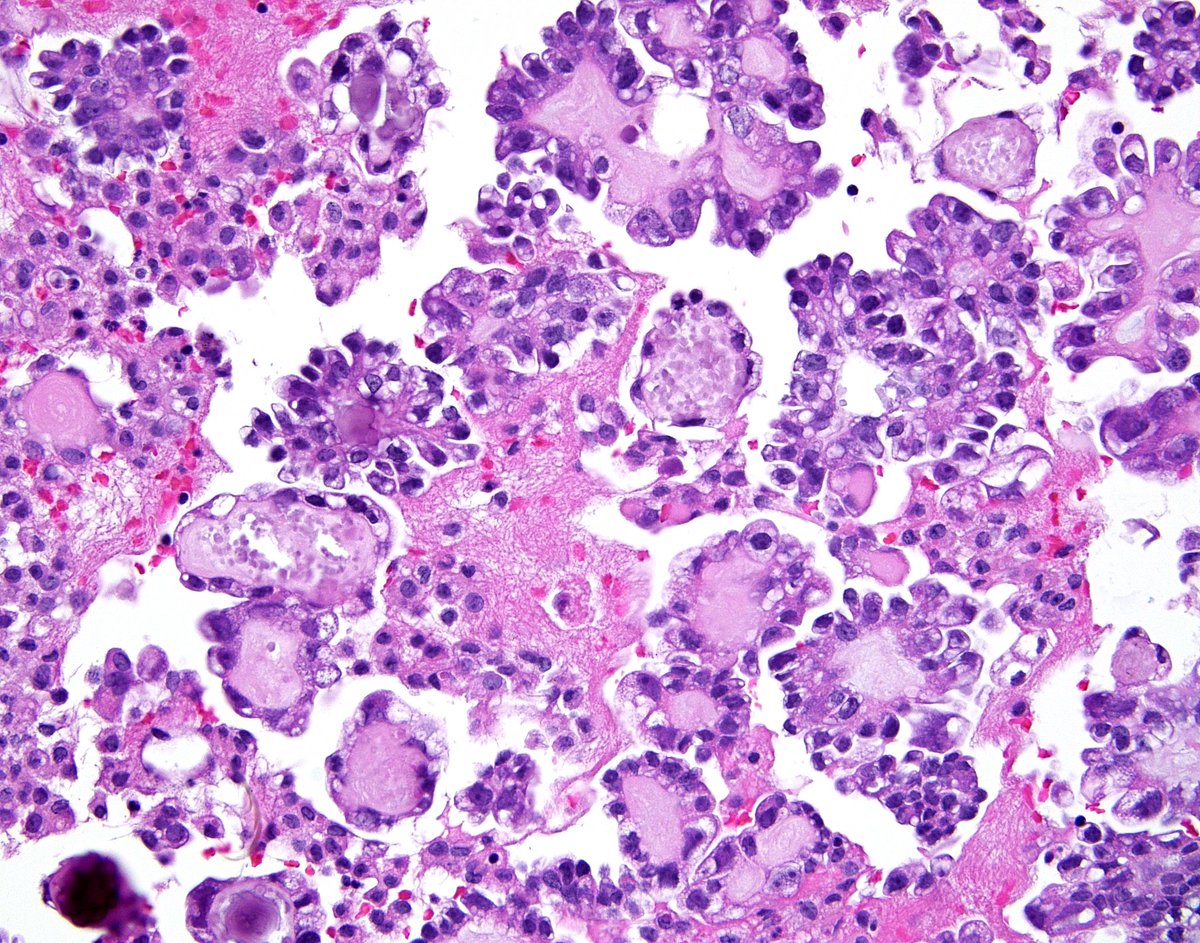

All the ingredients in this pleural fluid cell block for the diagnosis of a "Clear Cell Carcinoma" metastatic from the patient's known ovarian primary - hobnailed nuclei, globular structures with hyaline-type matrix, psammoma bodies and so called "raspberry bodies". See the

All the ingredients in this pleural fluid cell block for the diagnosis of a "Clear Cell Carcinoma" metastatic from the patient's known ovarian primary - hobnailed nuclei, globular structures with hyaline-type matrix, psammoma bodies and so called "raspberry bodies".